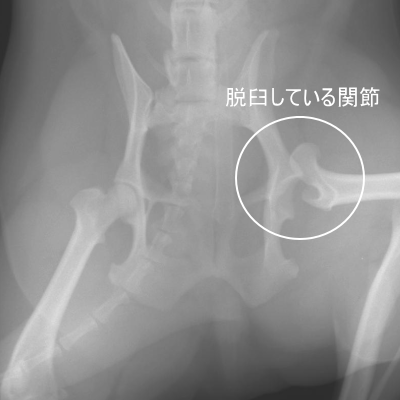

Case18症例18

股関節脱臼

犬に起きることが多いです。猫では交通事故での症例です。

【原因】

ジャンプの着地時や溝に落ちた、足が何かにひっかかった時など。

交通事故

【症状】

骨折ほどではありませんが脱臼直後はかなりの疼痛です。

三本足で歩く、患肢は着地しませんが軽く浮かしているような状態です。

【治療】

麻酔下で関節を戻してみる方法もありますが、麻酔が覚めたら再脱臼する確率が高いため、当院では外科的に整復するようにしています。

再脱臼を繰り返す場合、経過が長い場合は骨頭を切除する手術が適応になります。

【経過】

一週間くらい入院安静させてから退院となります。